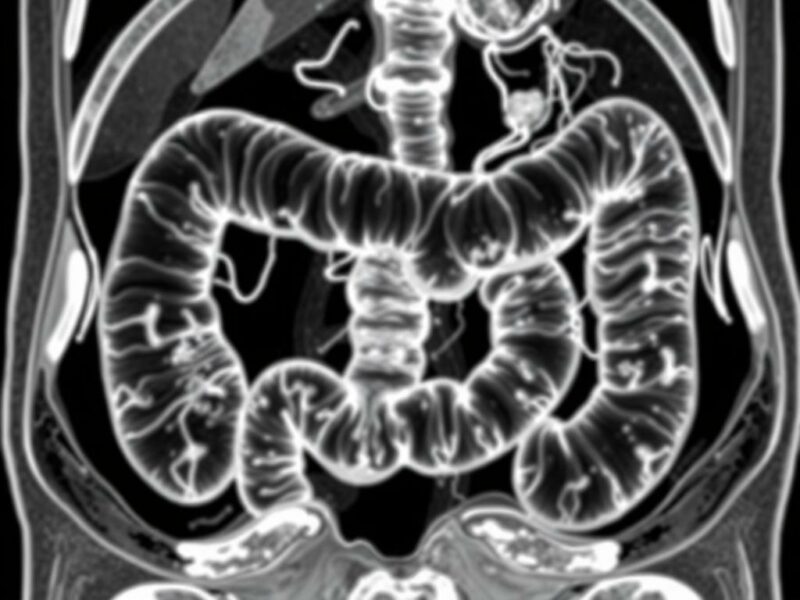

En la práctica habitual, el flujo diagnóstico suele ser: apendicectomía → informe histopatológico que identifica el tumor → decisión sobre tratamiento adicional o seguimiento → en caso necesario, estudios de imagen para descartar metástasis. Para evaluar la extensión y la presencia de enfermedad a distancia se recurren a técnicas como la tomografía computarizada (TC), la resonancia magnética (RM) y las imágenes funcionales específicas para tumores neuroendocrinos, como la PET con Ga-68 DOTATATE o el gammagrama con Octreoscan.

| TC abdominopélvica con contraste | Visualiza masa, ganglios y metástasis hepáticas | Si el tumor >1–2 cm o hallazgos histológicos agresivos |